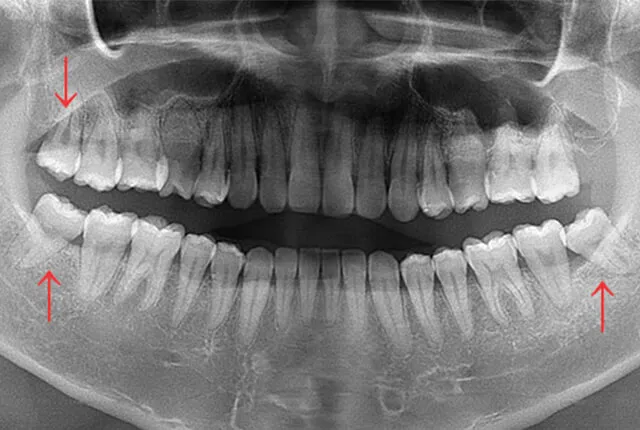

下顎の横向き親知らず

下顎の横向きの親知らずは、抜歯の難易度が高くなります。これは、親知らずが手前の7番にぶつかっているため、そのままでは抜けないからです。

この場合、歯を削る機械を使って親知らずの頭と根を分割し、頭の部分を先に取り出してから、残った根を抜いていきます。分割の回数は歯の状態によって異なり、1回で済む場合もあれば、3〜4分割が必要な場合もあります。

抜歯にかかる時間は15〜30分程度ですが、診察室に入ってから出るまでは1時間程度かかるとお考えください。術後は痛みや腫れが強く出る場合があり、4〜7日程度続くこともあります。